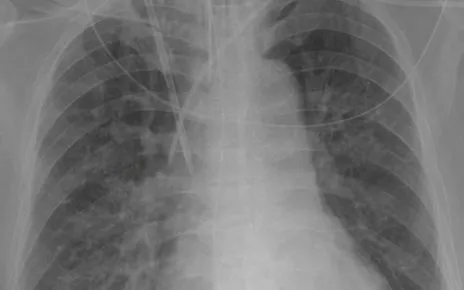

Kết quả xét nghiệm cho thấy tình trạng nhiễm trùng nặng, X-quang phổi ghi nhận hình ảnh viêm phổi thùy. Ngay sau đó, bệnh nhi được xử trí tích cực với thở oxy và điều trị phối hợp hai kháng sinh Vancomycin và Ceftriaxone theo phác đồ.

Sau 6 ngày điều trị, tình trạng bệnh nhi cải thiện rõ rệt: hết suy hô hấp, ngừng thở oxy, hết sốt, giảm ho, ăn uống tốt, phổi không còn ran. Phim X-quang phổi kiểm tra cho thấy tổn thương phổi cải thiện đáng kể, trẻ đủ điều kiện chuẩn bị xuất viện.